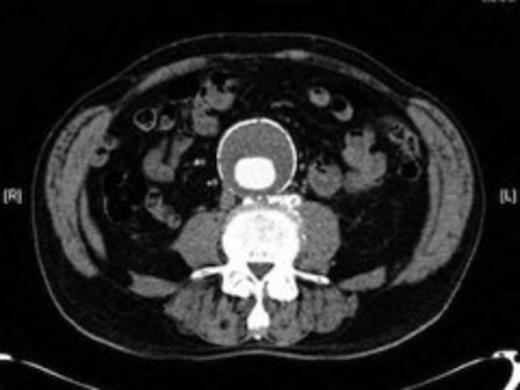

Four weeks following discharge the patient was re-admitted with feeling increasingly unwell, recurrent pyrexia, loss of appetite and mild shortness of breath on exertion. Physical examination was unremarkable except for a temperature of 38.3 centigrade. Blood tests on admission showed Hb 11.4 g/dl (11.5-16.0 g/dl), white cell count 13.1×109/L (4-9.2 x 109/L) and CRP 68mg/L (<3 mg/L). Contrast enhanced CT scan (Fig. 2,3) showed a 50 mm maximum retroperitoneal collection situated between the right kidney and the right iliac vessels. It contained a few loculi of gas. A diagnosis of postoperative right psoas abscess was made. The patient was started on intravenous broad spectrum antibiotics – Tazocin (Piperacillin+ Tazobactam) and Metronidazole. CT guided drainage was carried out using a 10 French gauge pigtail catheter locked pigtail (Meditech Flexima regular all-purpose drainage catheter sets with locking pigtail (Boston Scientific)) (Fig. 4). The isolation of E. coli from the collection with negative Hemocultures suggested a bowel source for the infection but no actual breach was demonstrable. The bowel surgeons ruled out colonic pathology.

A 50 mm maximum retroperitoneal collection situated between the right kidney and the right iliac vessels